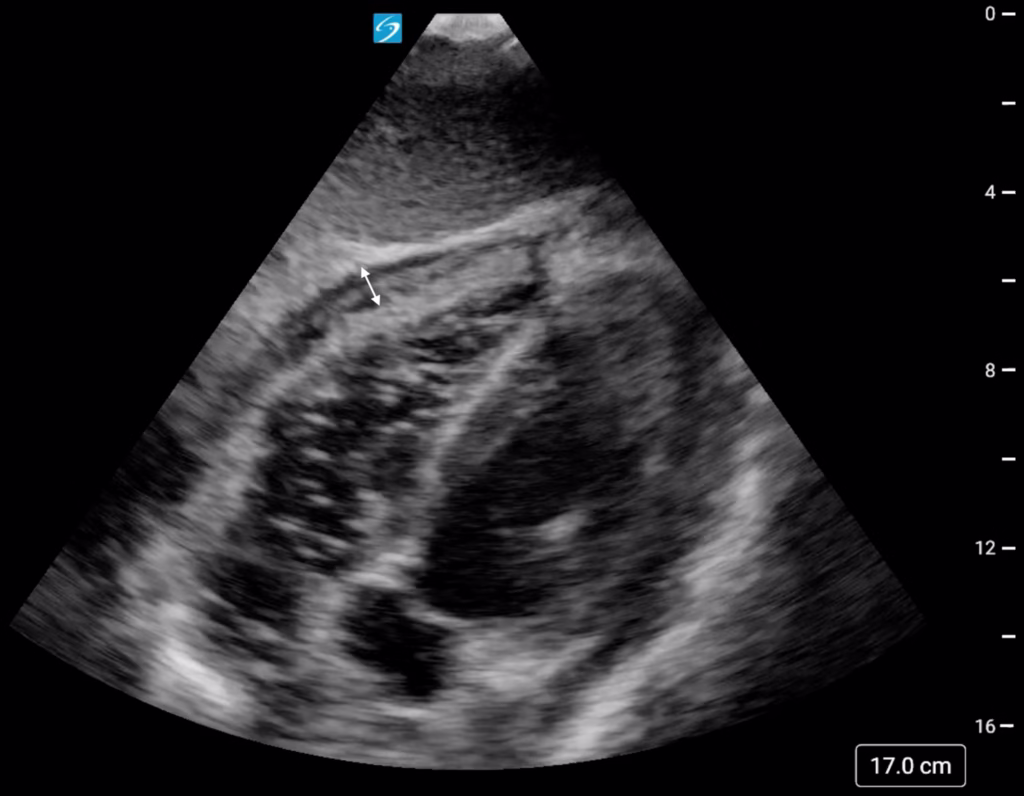

Repeat cardiac POCUS following aspiration of 50 mL of purulent fluid revealed a decrease in the volume of pericardial effusion and improved heart contractility which corresponded with an improvement in blood pressure to 128/106 mmHg (Figure 3, Supplementary Material S3).

Figure 3. Subxiphoid cardiac point of care ultrasound (POCUS) view revealing a decrease in the size of the pericardial effusion (double-headed arrow) following aspiration of 50 mL of purulent fluid during the repeated attempt at pericardiocentesis under POCUS-guidance.